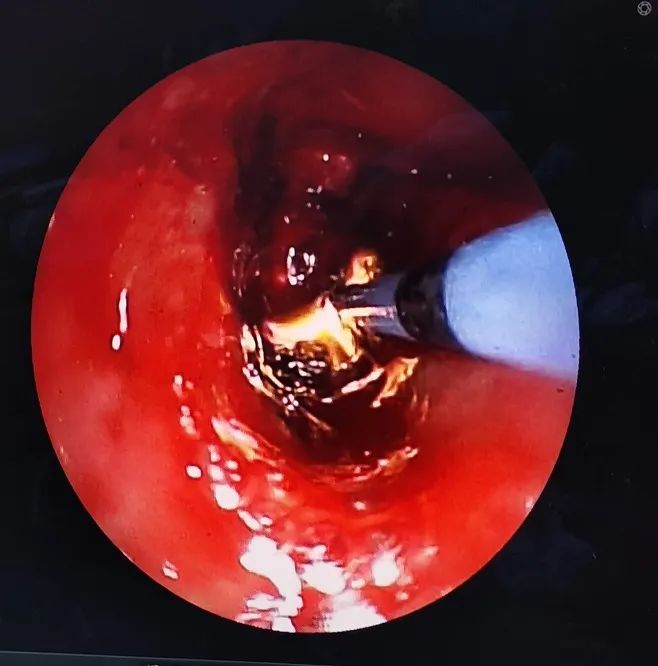

对气管内肿瘤进行冷冻切除

对气管内肿瘤进行APC消融